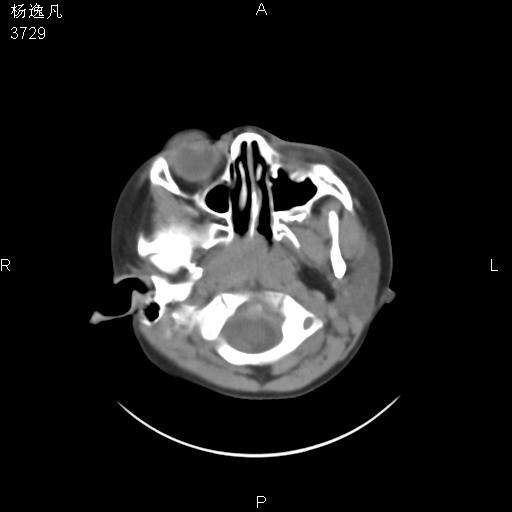

男性,5岁,面部受外伤,余无特殊

薄层

1、右面部及颞部软组织肿胀。

2、腺样体肥大。

头颅ct平扫未见明确外伤性征象,右侧面部及颞部软组织肿胀,后鼻腔软组织影增大,增厚,鼻咽顶部变窄,考虑鼻咽腺样体增值肥厚。